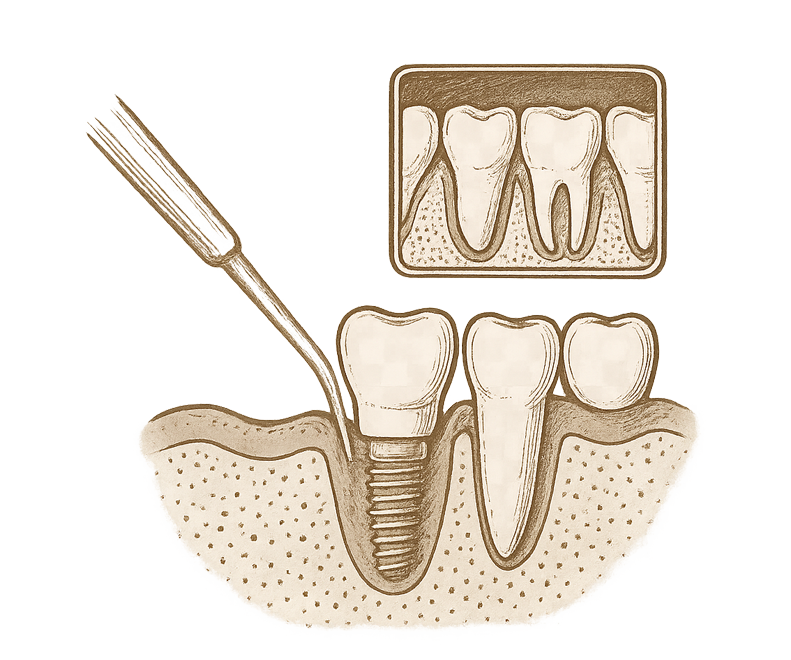

20 Yaş ve Gömük Diş Operasyonu

20 yaş dişleri (akıl dişleri), genellikle çene yapısında yeterli alan olmadığında gömülü kalır veya yarı sürmüş pozisyonda problem oluşturabilir. Gömük dişler; diş eti enfeksiyonlarına, çene ağrılarına, komşu dişlere baskı yaparak çürümelerine ya da dişlerde çapraşıklığa neden olabilir. Bu nedenle çoğu zaman cerrahi olarak çekilmeleri gerekebilir.

Gömük diş operasyonları, lokal anestezi altında ve steril cerrahi ortamda gerçekleştirilir. Kavi Diş Kliniği’nde bu işlem, uzman çene cerrahımız tarafından yapılır. Operasyon sonrası iyileşme süreci, kişiye göre değişmekle birlikte genellikle hızlı ve kontrollü ilerler.

Düzenli kontrollerde 20 yaş dişlerinin konumları panoramik röntgenlerle değerlendirilerek, müdahale gerekip gerekmediği anlaşılır. Gömük diş sorunlarıyla erken dönemde ilgilenilmesi, ileride oluşabilecek ağrılı ve enfekte durumların önüne geçmek açısından büyük önem taşır.